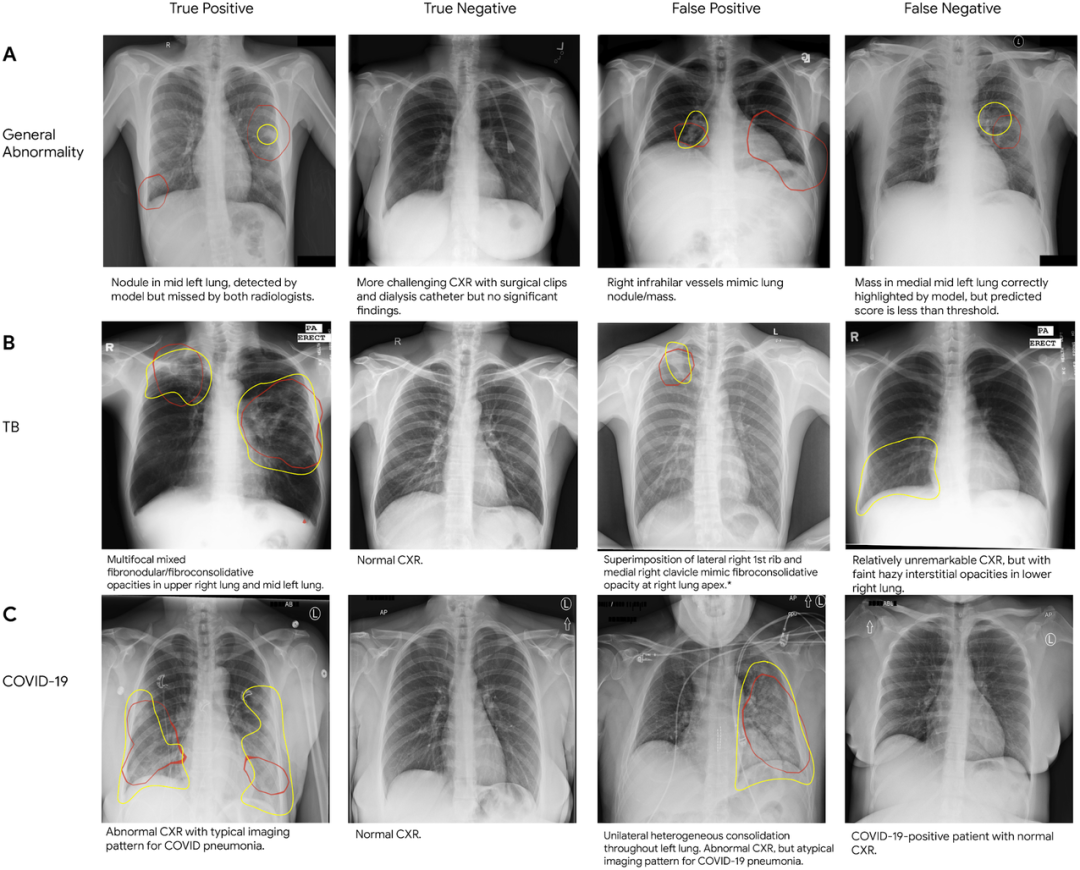

图丨对(A)一般异常、(B)结核病和(C)COVID-19 的真阳性、假阳性以及真阴性、假阴性的胸部 X 光片(CXR)进行采样。在每张 CXR 中,红色的轮廓表示模型识别时关注的区域(即类激活图),黄色的轮廓表示由放射科医生认定的感兴趣区域。